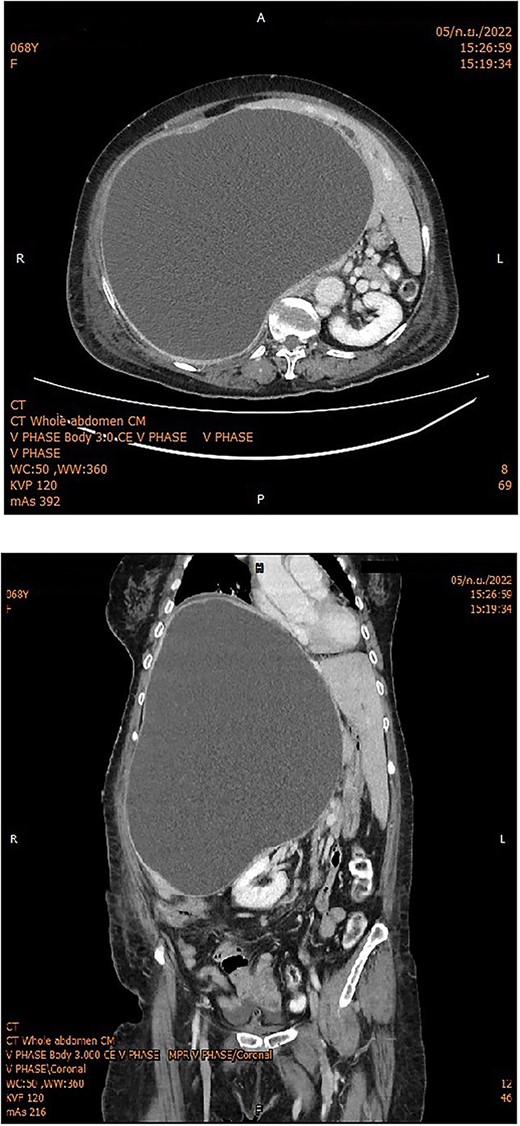

She was clinically diagnosed with acute cholangitis. Possible differential causes were choledocholithiasis or complications of hepatic cysts. The patient was sent for a CT scan, which revealed an increase in hepatic cyst size (22 × 24 × 32 cm), causing increased IHD dilation in the left hepatic lobe and hepatic segment 5, without common bile duct dilation (Fig. 1).

Whole abdomen enhanced CT showed a huge hepatic cyst occupying the right lobe of the liver with intrahepatic bile duct dilatation in the left lobe; the right kidney was displaced into the midline.